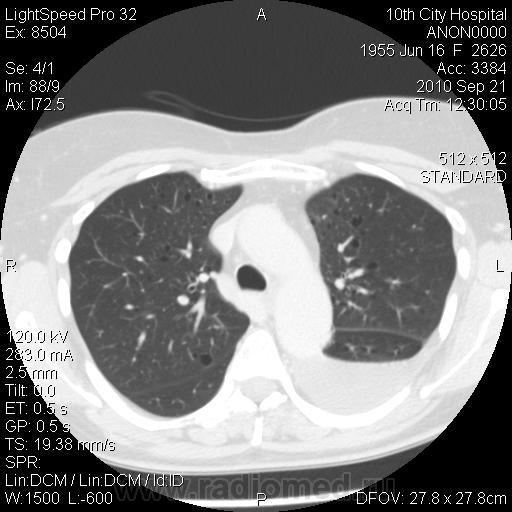

Немного предыстории: женщина поступила в плановое хирургическое отделение, по поводу кистозного образования в проекции головки ПЖ. (месяц назад лечилась по поводу острого панкреатита в другой больнице). В настоящее время на УЗИ - киста в области головки ПЖ. Мы сделали КТ - типичная карина псевдокисты в области головки. Но меня заинтересовали легкие. Из анамнеза узнал, что с 2004 года у пациентки постоянные рецидивирующие хилотораксы (лечилась во множестве больниц, диагноз не установлен). Вообщим сделали вчера КТ ОГК - что и выставляю.

Прошу прощения, сразу не заметил - выложенная реконструкция сделана на ВЫДОХЕ.

В области бифуркации лёгочного ствола киста? средостения. Гидроторакс слева. Что я пропустила?

Да нет, я решил, что это лимфангиолейомиоматоз...

Больше в нижних отделах эмфизаматозные буллы различных размеров, междолевые плвра уплотнены, слева в плевральной полости выпот.

А мне кажется это не просто буллы... Как и писал выше - склоняюсь к LAM